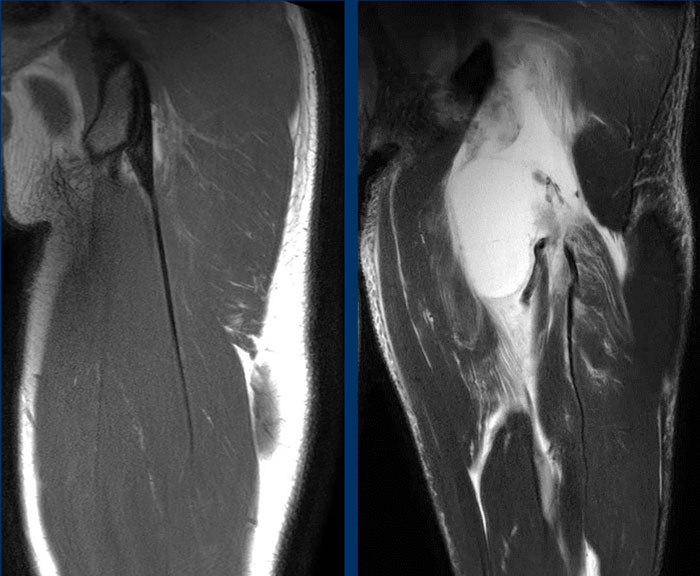

Nel caso qui sopra la lesione (fig RM a destra) riguarda invece la componente libera prossimale del tendine congiunto, avulso dalla sua inserzione ossea. La lesione è classificabile come 4 grado. A sinistra l'immagine RM del tendine normale.